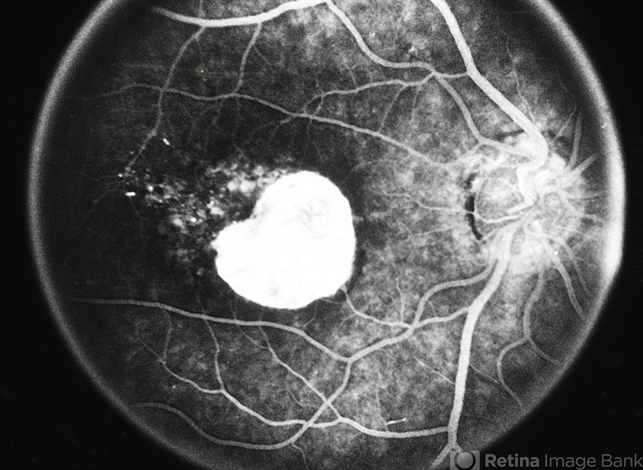

- macular atrophy

- Macular atrophy.